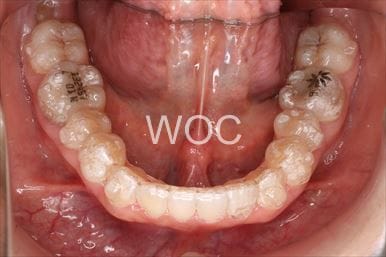

治療後1

- 年齢:20歳女性

- 主訴:出っ歯が気になる

- 基本矯正料金:120万円

- 治療期間:1年7ヶ月

- 抜歯部位:上顎両側第一小臼歯